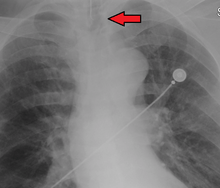

An endotracheal tube in good position on CXR. Arrow marks the tip.

An endotracheal tube not deep enough. Arrow marks the tip.

No single method for confirming tracheal tube placement has been shown to be 100% reliable. Accordingly, the use of multiple methods for confirmation of correct tube placement is now widely considered to be the standard of care.[32] Such methods include direct visualization as the tip of the tube passes through the glottis, or indirect visualization of the tracheal tube within the trachea using a device such as a bronchoscope. With a properly positioned tracheal tube, equal bilateral breath sounds will be heard upon listening to the chest with a stethoscope, and no sound upon listening to the area over the stomach. Equal bilateral rise and fall of the chest wall will be evident with ventilatory excursions. A small amount of water vapor will also be evident within the lumen of the tube with each exhalation and there will be no gastric contents in the tracheal tube at any time.[31]

Ideally, at least one of the methods utilized for confirming tracheal tube placement will be a measuring instrument. Waveform capnography has emerged as the gold standard for the confirmation of tube placement within the trachea. Other methods relying on instruments include the use of a colorimetric end-tidal carbon dioxide detector, a self-inflating esophageal bulb, or an esophageal detection device.[33] The distal tip of a properly positioned tracheal tube will be located in the mid-trachea, roughly 2 cm (1 in) above the bifurcation of the carina; this can be confirmed by chest x-ray. If it is inserted too far into the trachea (beyond the carina), the tip of the tracheal tube is likely to be within the right main bronchus — a situation often referred to as a "right mainstem intubation". In this situation, the left lung may be unable to participate in ventilation, which can lead to decreased oxygen content due to ventilation/perfusion mismatch.[34]